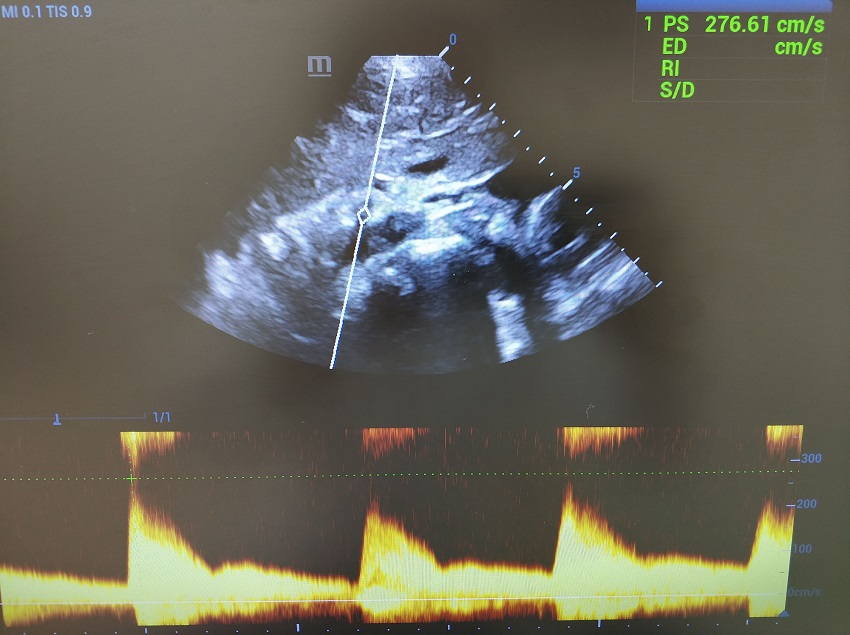

Повторяем маневр, контрольный объем скользит в чревный ствол. Прибор переходит на визг, ручка Scale вправо - увеличиваем шкалу и пульсация затихает. Калипер поднимается на вершину систолического пика, PSV 276 см/сек. Максимум ли? Переходим в режим постоянно волнового CW-допплера, фокус в зону истока чревного ствола. Да, максимум.

В заключение: Синдром Данбар (транзиторная абдоминальная ишемия). Компрессия чревного ствола ножками диафрагмы. Перегородки желчного пузыря – вариант нормальной анатомии.